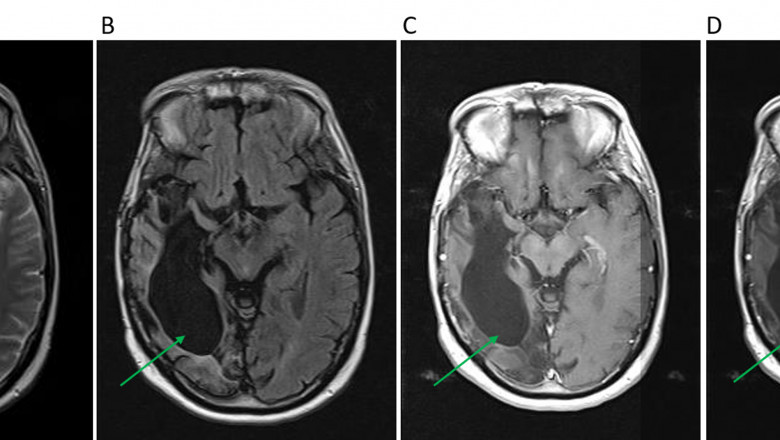

Recurrent Glioblastoma Multiforme Treatment involved Glial cells, which is a type of brain cancer

Glioblastoma multiforme is a heterogeneous social affair of improvements (it acts contrastingly in various individuals) and can differ when it returns or repeats. It will in everyday repeat inside 6-8 months in various patients. Notwithstanding the way that there is no standard recurrent glioblastoma multiforme treatment, patients with this wickedness have different treatment choices open to them. Glioblastoma's charge their bearing into ordinary mind tissue diffusely and conflictingly, which makes them careful terrible dreams. Signs and indications of GBM unite seizures, cerebral anguish, twofold or blurred vision, disgorging, and bother in talking.